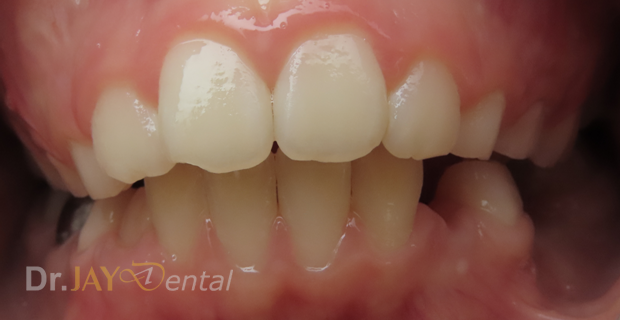

Severe crowding , parent had gone for a consult with 4 Orthodontist to resolve crowding. Orthodontist recommended extraction of multiple teeth to resolve crowding and straighten teeth. At Dr.Jay Dental , Dr. Jay finished the case with no extractions of teeth and just expansion of upper and lower jaws to accommodate all teeth.

Before

After